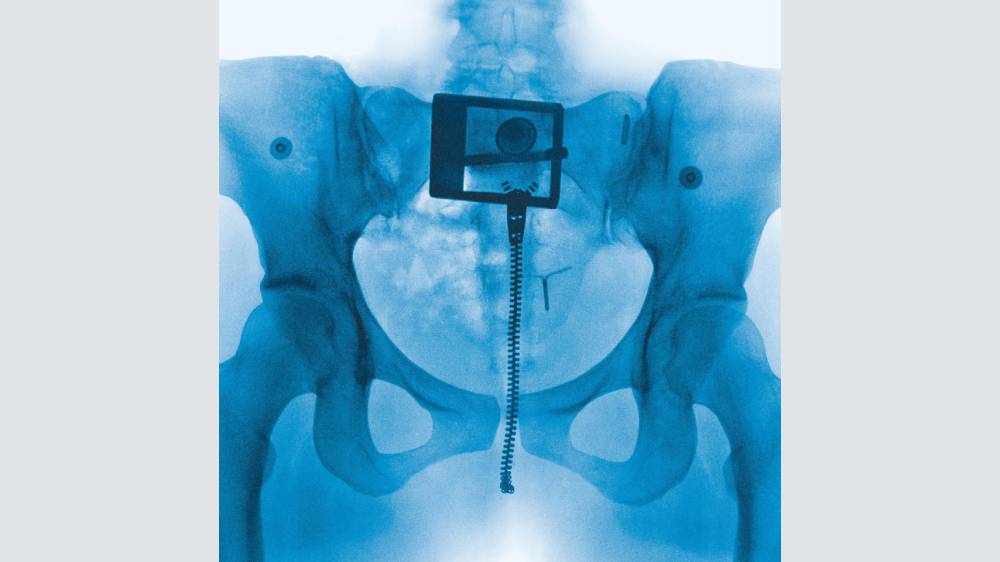

And lyrically, it’s as revealing as the x-ray of her pelvis on the album’s cover. There are heavy emotions in every song, which she’s said stem in part from a breakup, an eating disorder and general anxiety and self-loathing; there are references to punching mirrors, stage fright, ego death, obsessing over body weight, even bodily functions. The themes might verge into oversharing for some, but it’s always been a part of her persona, and the upshot is about confronting, accepting and/or resolving one’s own messiness and starting over (hence the title).